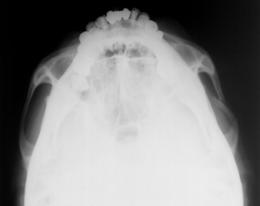

⑥ 両側同時頬骨弓軸位撮影法・・・頬骨弓単純撮影法にはさまざまな撮影法があるが被検者に出来る限り負担の掛からない撮影ポジションで軸位像を得るには通常行われている術中ポータブル撮影法が“患者さんに優しい撮影法技術”である。この撮影法は頬骨弓面と受像面を平行としX線を下顎方向よりこれらの面に対して垂直入射とするだけの簡単な撮影法である。

自然な仰臥位においての両側同時頬骨弓軸位像撮影法とその画像